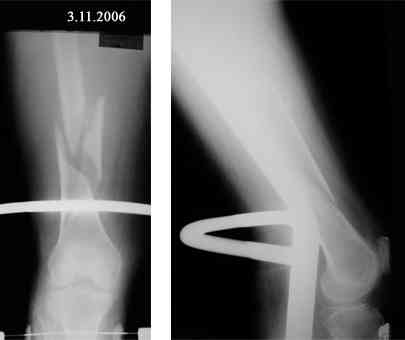

Re: Оскольчатый перелом бедра. Помогите определиться с дальнейшей тактикой

Представляю вашему вниманию снимки в динамике